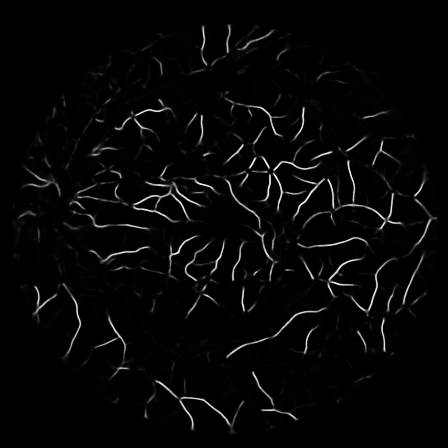

To justify the performance of our model, we compare the 4 metrics with 8 representative previous works from all 3 open-access datasets. The comparison results presented in Table 1 show that our MP-Net model outperforms the state-of-the-art methods regarding accuracy and in all three datasets, which meter the practical prediction quality and the overall prediction quality independent on thresholding specifications. The advancement is greater in the DRIVE dataset. It’s related to the fact that the DRIVE dataset contains more thin vessels, which is the main target of our model. Specificity is also the highest in DRIVE and CHASE_DB1 while sensitivity is highest in STARE. Particularly, our method outperforms ML-UNet [2] and JL-UNet [4] which adopt a different multi-class approach to also especially tackle the thin-vessels challenge. Figure 2 shows an example of our segmentation maps on DRIVE. As can be seen, most thin vessels and boundary areas have been meticulously picked up.